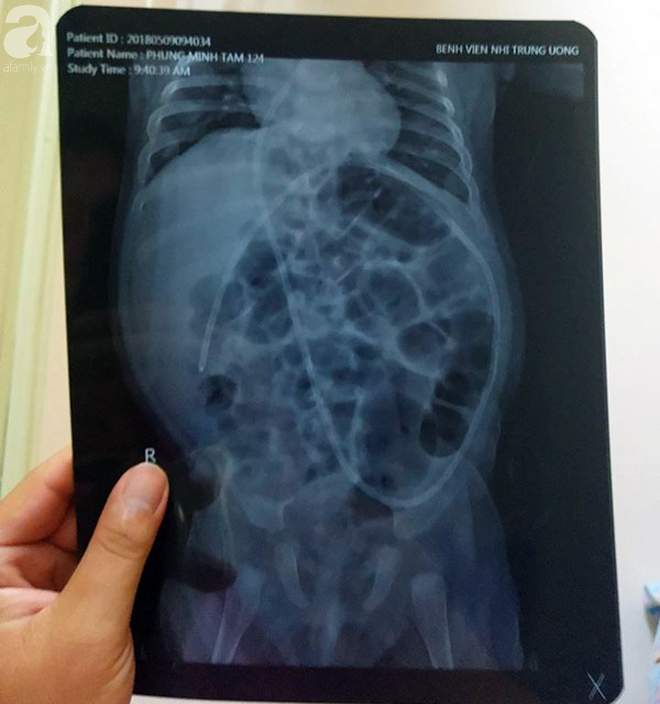

Tại đây, các Bác sĩ chẩn đoán bé Minh Tâm bị mắc bệnh chậm phát triển, não úng thủy. Tính đến thời điểm hiện tại bé đã phải trải qua 5 lần phẫu thuật để cứu lấy mạng sống.

"Mỗi lần phẫu thuật là con phải khoan sọ não khiến chúng tôi như rụng rời chân tay, nước mắt chúng tôi đã cạn khô, không còn để khóc thương con nữa…" anh Tú nghẹn ngào.